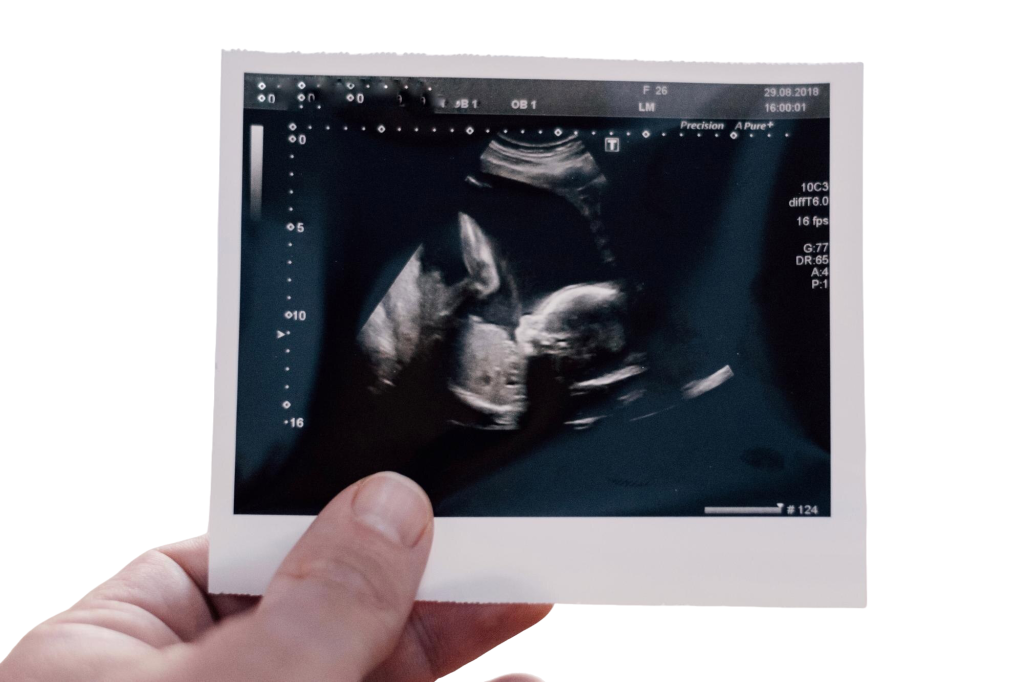

At Aakash Fertility Centre, we offer 3D Ultrasound Imaging, a modern tool that creates detailed three-dimensional images of internal structures. This helps doctors see the fetus, uterus, and other tissues clearly, making assessments and treatment planning more accurate.

3D ultrasound combines many 2D images taken at different angles to create a three-dimensional view. This gives more detail than traditional 2D ultrasound, helping doctors understand conditions better.

- 3D ultrasound improves diagnostic accuracy. In obstetrics, it helps detect fetal anomalies. In gynecology, it provides detailed views of the uterus for conditions like fibroids and polyps.